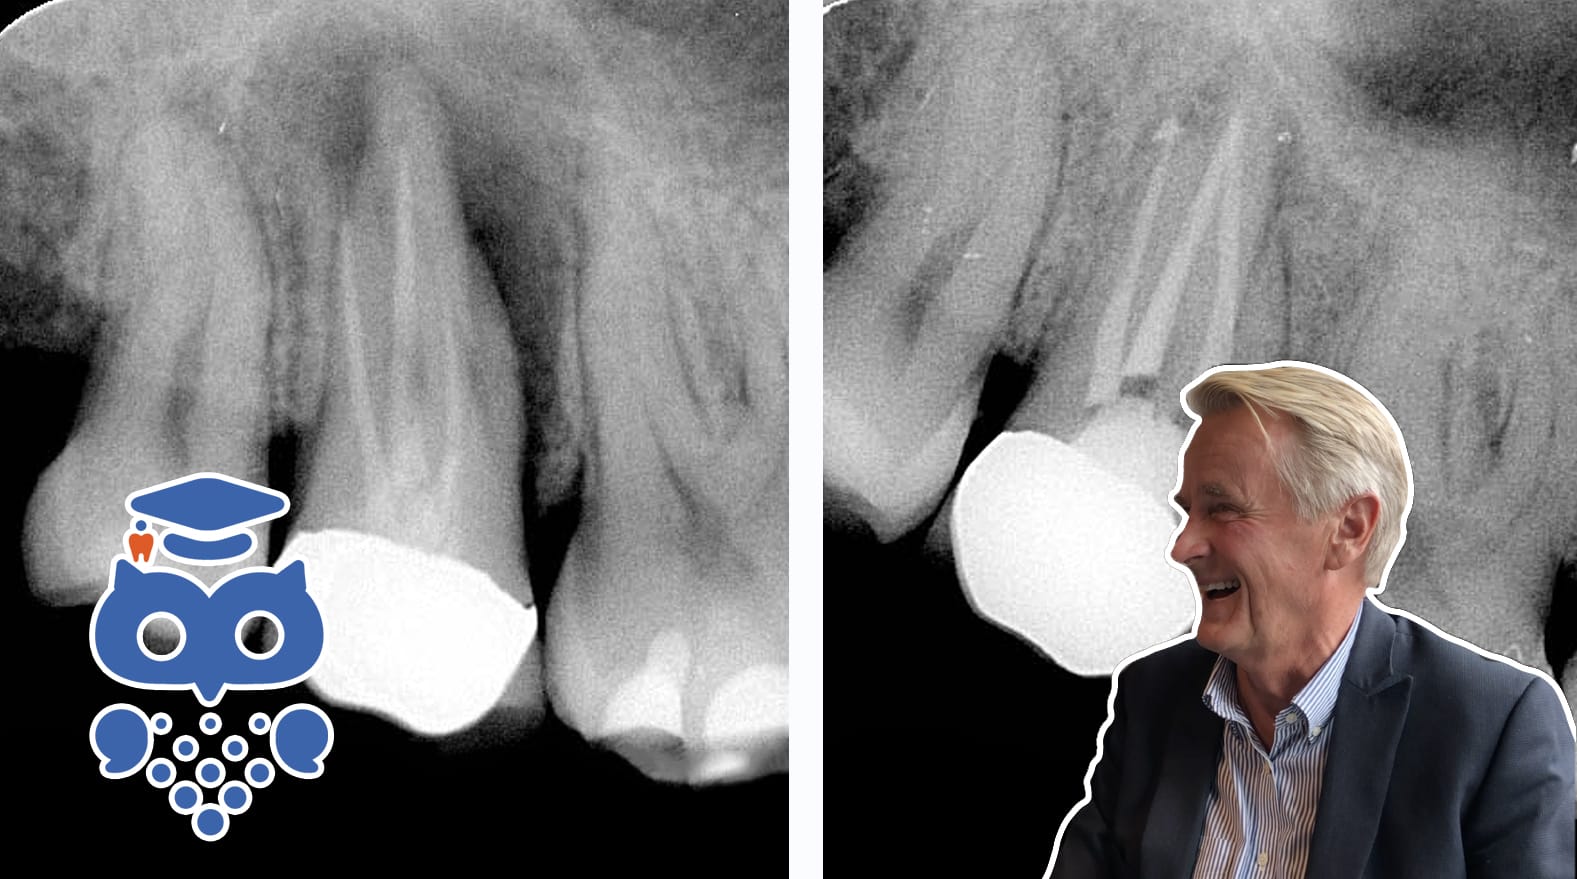

Rotfyllning förseglar rotkanalen för att förhindra bakteriekolonisering och läckage. Vanliga material är guttaperka och sealer, medan cement används vid specifika indikationer. Antimikrobiella egenskaper kan vara fördelaktiga men måste balanseras mot vävnadstoxicitet.

Rotfyllningsmomentet är den avslutande delen av den endodontiska behandlingen och syftar till:

• Att försegla tanden och förhindra mikroorganismer från att kolonisera rotkanalsystemet.

• Att kapsla in eventuella kvarvarande bakterier i rotkanalssystemet för att förhindra exponering för den periradikulära vävnaden.

• Att förhindra läckage av nutrienter till rotkanalssystemet från kronan och den periradikulära vävnaden.

De vanligaste rotfyllningsmaterialen består av ett kärnmaterial och en sealer, men på speciella indikationer kan det förekomma att kanalsystemet fylls partiellt eller helt med ett cement. En nackdel med att fylla hela kanalsystemet med ett cement är svårigheten att avlägsna materialet vid behov av revision eller utföra rotrymning inför pelarterapi.